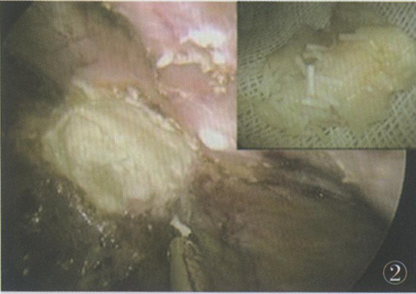

600mg(4mm×0.8mm圆柱状颗粒),2周前查CT发现肝占位性病变而就诊于我院。实验室检查:AFP 2.1 ng/ml,CEA l.6 ng/ml,CA199 3.2 U/ml。CT提示:肝左叶占位性病变,考虑肝转移性癌可能,病灶周围局部肠粘连(图1)。

图1术前CT检查1A:(平扫期)肝脏左外叶低密度病灶,与周围肠管粘连(箭头);1B:(动脉期)病灶强化不明显(箭头);1C:(静脉期)病灶仍表现呈低密度(箭头)

(1)胃癌等腺癌肝转移的患者CT检查增强早期可见病灶边缘强化、中心为低密度,晚期时相病灶边缘为低密度。本例患者CT检查结果增强早、晚期病灶无明显强化(图1),且结合病史术中有植入用缓释氟尿嘧啶的使用情况,诊断应考虑为植入用缓释氟尿嘧啶的局部并发症,但其相关报道少,所以导致术前误诊。